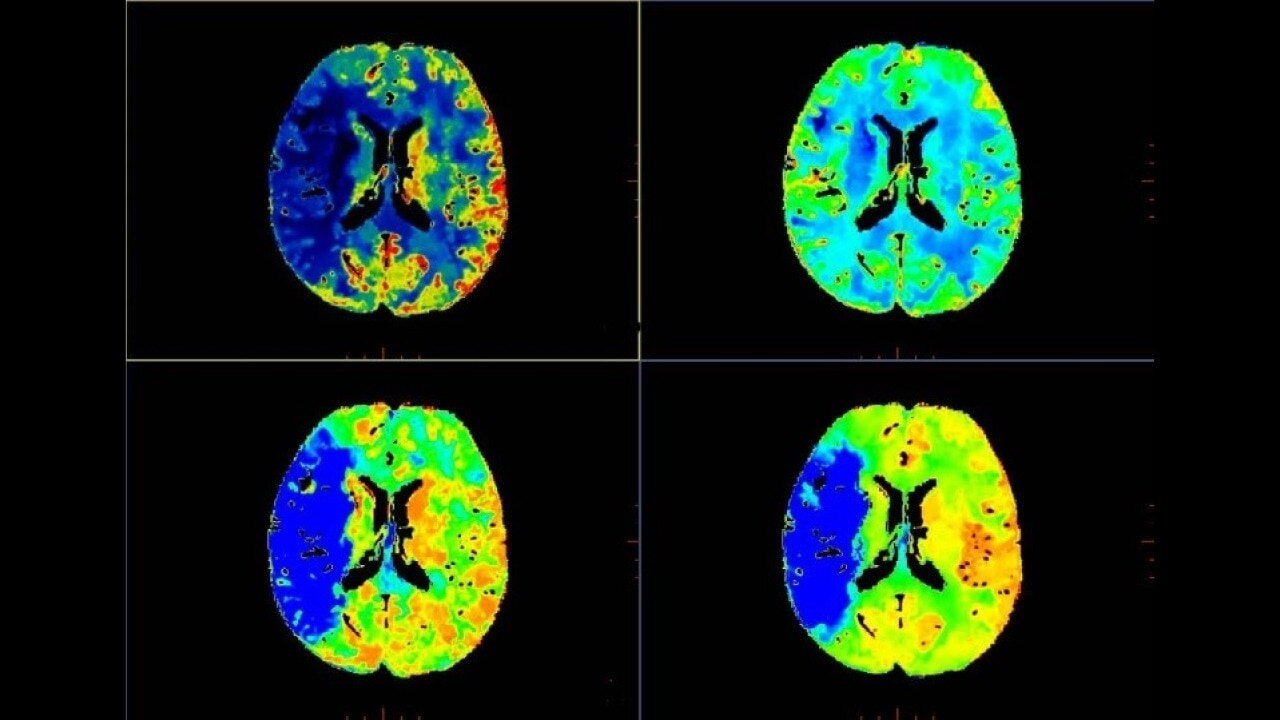

Brain perfusion

Easy-to-use automated workflow for CT stroke and tumor angiogenesis evaluation

Brain stroke protocol

• Image Registration to minimize the effects of patient movement

• Bone Removal to remove the cranium automatically from the dataset

• Deep Learning brain ventricle segmentation to prevent ventricular matter inclusion in quantitative results and improve visual inspection of the maps

• Automated selection of arterial input and venous output. Both can be easily adjusted if needed.

• Automated generation of all functional maps: Blood Flow, Blood Volume, Mean Transit Time, and Transit Time to IRF Peak (Tmax)

• Automatically define the symmetry plane to be used for mirroring ROIs and relative thresholds

• Tissue Classification enables the visualization of regions that are segmented from absolute or relative values, customizable thresholds and user selectable input maps

• Mismatch volume and ratio are calculated from the modified perfusion volume and low perfusion volume ROIs